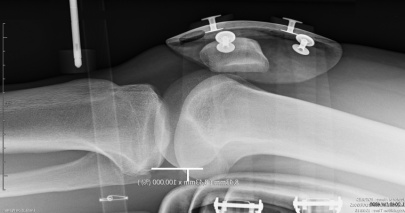

Die automatisierte dynamische Laximetrie für einen neuen Ansatz in der Untersuchung der Funktion der Bänder

Die LDA® erlaubt die Messung und Berechnung neuer Werte um eine hochkomplexe radiologische Untersuchung der Funktion der Kniebänder zu ermöglichen.

Der LDA® Test ist eine unverzichtbare Ergänzung der medizinischen Bildgebung in der Untersuchung des VKB's. Er erlaubt eine dynamische Vorstellung durch die Erfassung der Widerstandskurven der Bänder.

Das GNRB Radio ist speziell gestaltet für einen rationellen Einsatz in der Radiologischen Praxis

Der LDA © Test ist einfach, schnell und komfortabel für den Patienten (liegend auf der Radiologie Tisch). Er ist innerhalb von Minuten während der radiologischen Untersuchung durchführbar.

Das GNRB Radio besitzt eine 5 sekündige Sperrfunktion für die Translation in der oberen Position, um Röntgenbilder zu erfassen.

Eine patentierte Messmethode

Der Lachmann Test ist mit dem GNRB Radio vollständig automatisiert

Die Werte der Fixation von Knöchel und Oberschenkel werden gespeichert. Die LDA® Software synthetisiert und vergleicht sofort die an beiden Knien vorgenommenen Messungen, durch die Vermessung der Steigungen der Widerstands-Kurven der VKBs (Innovation Genourob)

Gezeigtes Beispiel : Präoperative Kontrolle

Δ 134 = 6 mm, Δ P2 = 2

Komplette Ruptur

Objektivierung eines klinischen Lachmann-Tests